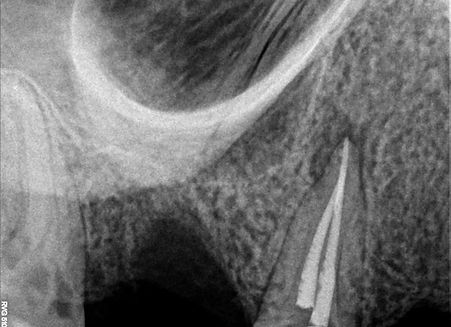

RTG kontrolne po 6 miesiącach od leczenia, widoczne gojenie sie zmian